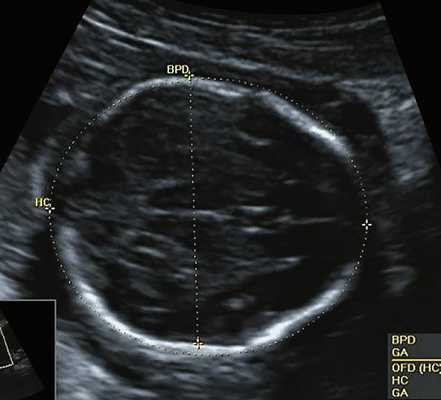

- БПР - бипариетального размера головки плода;

- БПР — бипариетального размера головки ;

| Набл. 1. 24,3 нед. | БПР - 25,3 нед. ОГ - 24,6 нед. Аномально повышенная бороздчатость и выпуклость извилин нижнемедиальной поверхности височных долей (рис. 1а). | Торакоабдоминальное соотношение - 66,7% (рис. 1б) Длина ребра - среднее для 16 нед. | Бедренная кость 19,6 мм (47,8% от должной), изогнута ("телефонная трубка") (рис. 1в). Остальные кости - среднее для 15 нед. | Уплощенные тела поясничных позвонков. |

| Набл. 2. 20,3 нед. | БПР - 21,5 нед. ОГ - 20,3 нед. Уплощенный затылок. Выпуклые темпоральные бугры (рис. 2а). Аномально повышенная бороздчатость и выпуклость извилин нижнемедиальной поверхности височных долей (рис. 2б). | Торакоабдоминальное соотношение - 63,3% (рис. 2в) Окружность груди - среднее для 18 нед. Длина ребра - среднее для 15 нед. | Бедренная кость 17,7% (61% от должной), изогнута ("телефонная трубка") (рис. 2г). Остальные кости - среднее для 13-14 нед. | Гипоплазия костей носа. |

| Набл. 3. 24 нед. | БПР - 30 нед. ОГ - 27,2 нед. Уплощенный затылок. Выпуклые темпоральные бугры (рис. 3а). Аномально повышенная бороздчатость и выпуклость извилин нижнемедиальной поверхности височных долей (рис. 3б). | Торакоабдоминальное соотношение - 56,6% (рис. 3в) Окружность груди - среднее для 20 нед. Сердце/грудь (см 2 ) - индекс 0,6. | Бедренная кость 23,1 мм (57% от должной), изогнута ("телефонная трубка") (рис. 3г) Остальные кости - 50% для 15-16 нед. Нормальная установка пальцев кисти (рис. 3д). | Многоводие. |

| Набл. 4. 26,5 нед? | БПР - 22,6 нед. ОГ - 22,6 нед. Форма - трилистник (рис. 4а). Боковые желудочки - 22 мм, высокий лоб, расширенный родничок, сагиттальный шов (рис. 4б). | Торакоабдоминальное соотношение - 65,7% (рис. 4в). Окружность груди - среднее для 23 нед. Колоколообразная форма. | ДБ - 23 мм (51% от должной). Остальные кости - 50% для 15-17 нед. Нормальная установка пальцев кисти (рис. 4б). | Уплощенные тела поясничных позвонков (рис. 4г). |

Примечание. БПР - бипариетальный размер, ОГ - окружность головы, ДБ - длина бедренной кости.